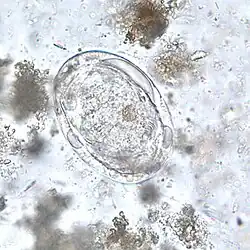

| Schistosoma japonicum | 90 × 70 µm (68–100 × 45–80 µm). | Owalne; mały kolec na tylnym biegunie może być haczykowaty lub mieć kształt guzka. Żółte lub żółtobrązowe, w środku zawierają dojrzałe miracidium. | Kał | ![]() |